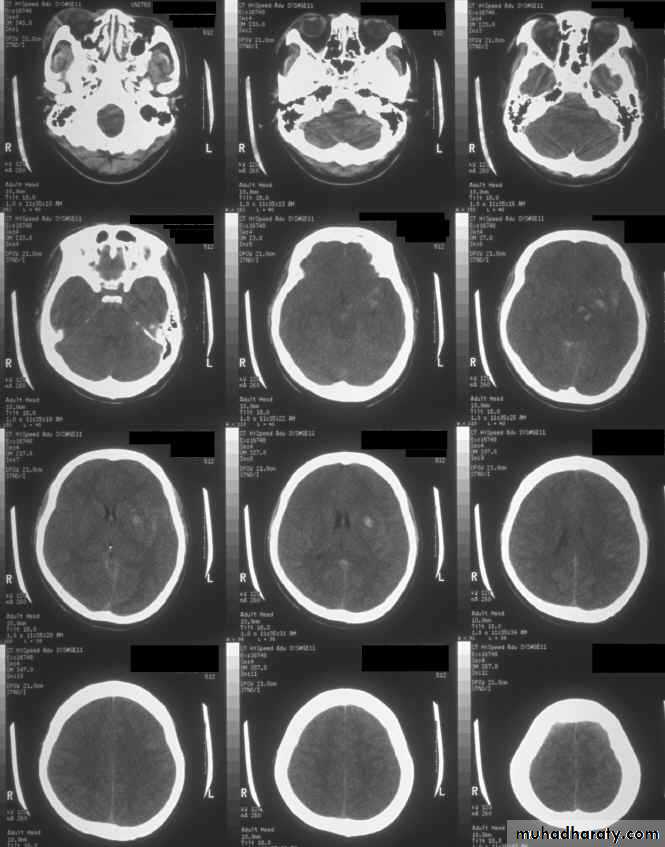

These are areas of bruising and swellings with intact pia arachnoid, localized or generalized oedema and haemorrhage due to tearing of blood vessels.3. Cerebral Contusion

Clinical presentations:1. Prolonged periods of unconsciousness.

2. Focal neurological deficits that persist for longer than 24 hours.

CT scans demonstrates contusions as small areas of haemorrhage in the cerebral parenchyma.

Contusions may resolve with the accompanying deficits or they may persist.